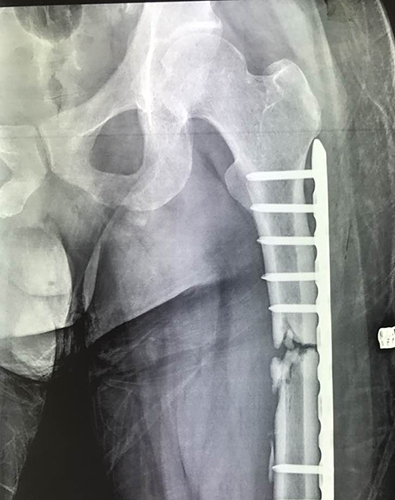

2018年12月24日,十堰市太和医院,采用HemaClear用于双下肢截肢患者,股骨骨不愈合病灶清除+取髂骨植骨+双钢板内固定+含抗生素人工骨植入术!

股骨骨折处,在股骨近端,靠近髋骨

传统气囊止血带(宽10cm左右),其无法应用于近根部手术;然而HemaClear(宽2~3cm),较为窄,发挥特有优势,解决气囊止血带的不足,填补了此类手术无止血带可用的临床空白!